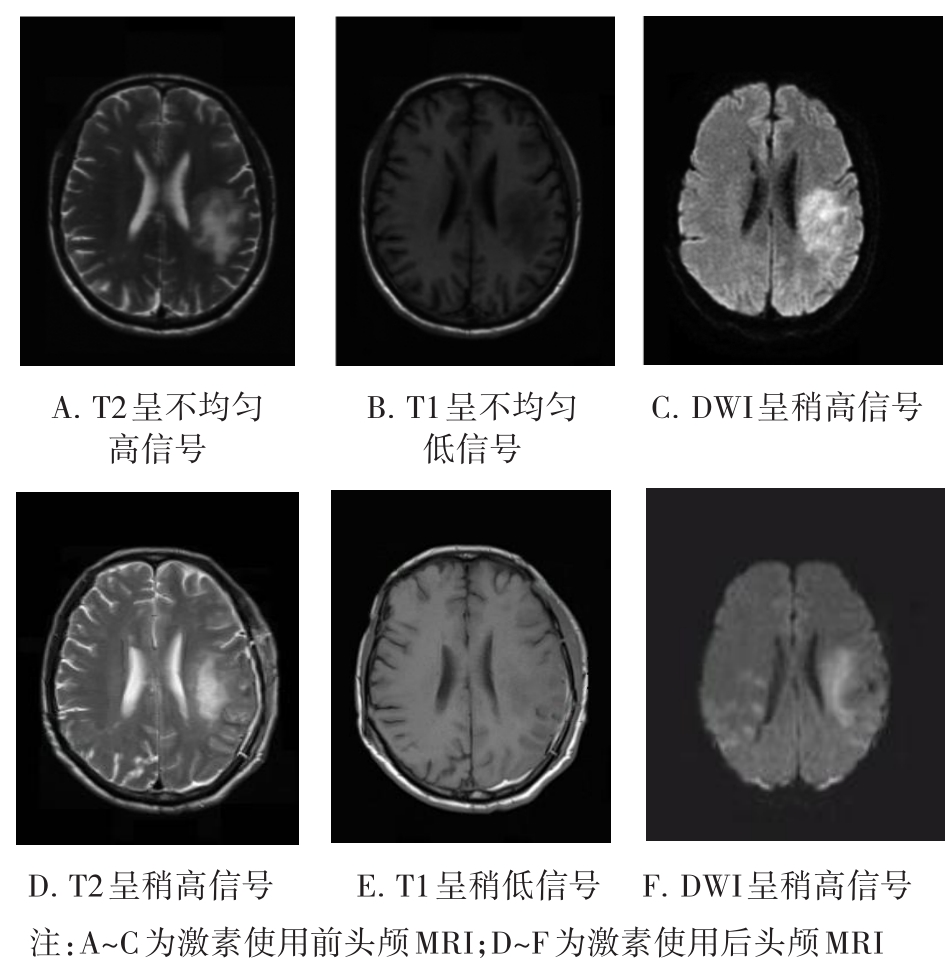

• 肿瘤样脱髓鞘病变报道3例

2023, 48(5):614-617. DOI: 10.13406/j.cnki.cyxb.003183

摘要 (95) HTML (24) PDF 1.29 M (241) 评论 (0) 收藏

摘要: